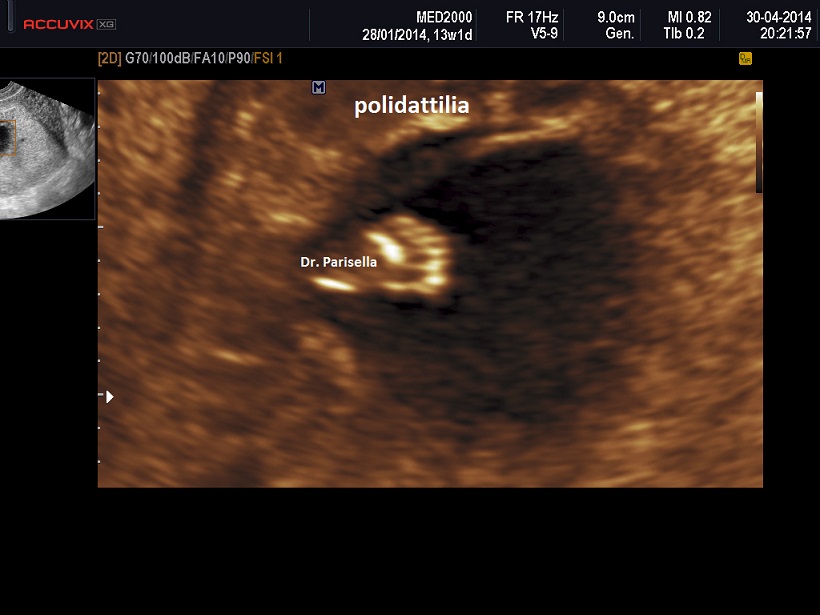

polidattilia